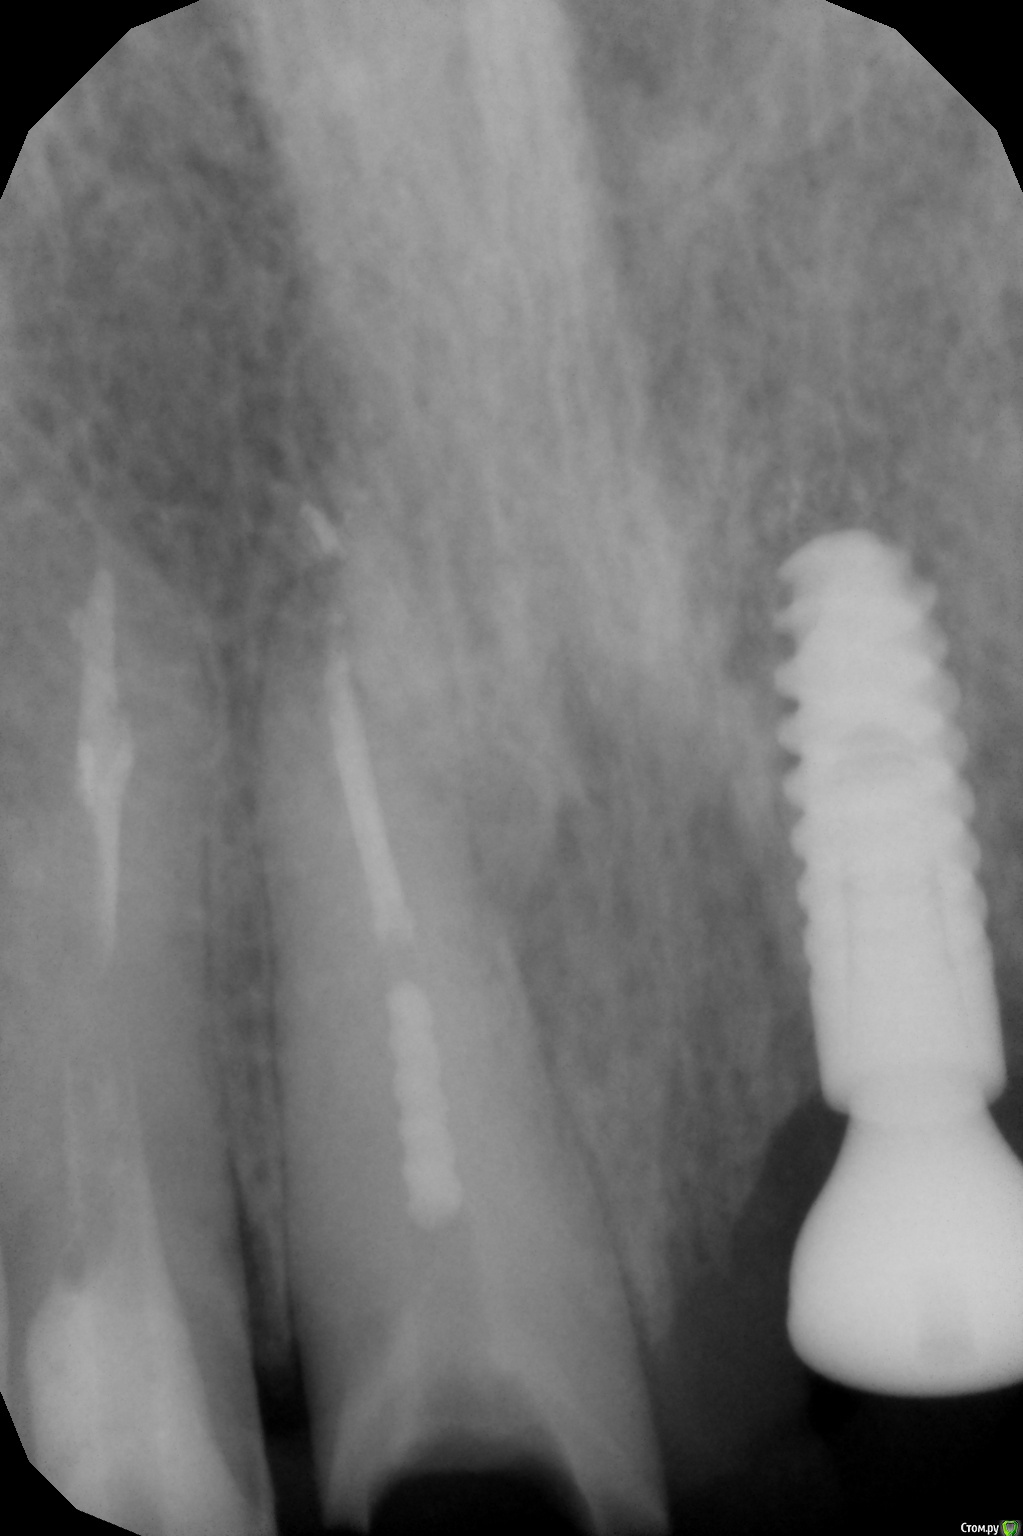

DmitrySH Опубликовано 10 октября, 2016 Поделиться Опубликовано 10 октября, 2016 Добрый день, коллеги.. Подскажите, как возможно провести эндодонтию в такой ситуации? Какие способы используете? Или это проходить вслепую только возможно?IMG_0458.JPG Если не брать во внимание разрушение зуба и показания к удалению ( это выше уже обсудили), то вполне нормально можно лечить. До фуркации аккуратно у/з с хлоркой Далее тонкими (06-08) к-файлами осуществляется навигация на всю рабочую длину. Кончики файлов предварительно надо подгибать в сторону канала. Вот 35. Только там еще и склерозировано все было и резорцин. http://forum.stom.ru/topic/21394-alaverdy/?p=428792 Ссылка на комментарий

ARislanV Опубликовано 12 октября, 2016 Поделиться Опубликовано 12 октября, 2016 Добрый день, коллеги.. Подскажите, как возможно провести эндодонтию в такой ситуации? Какие способы используете? Или это проходить вслепую только возможно?IMG_0458.JPGТам три канала что ли?? Какие у вас там новости, вылечели? Ссылка на комментарий